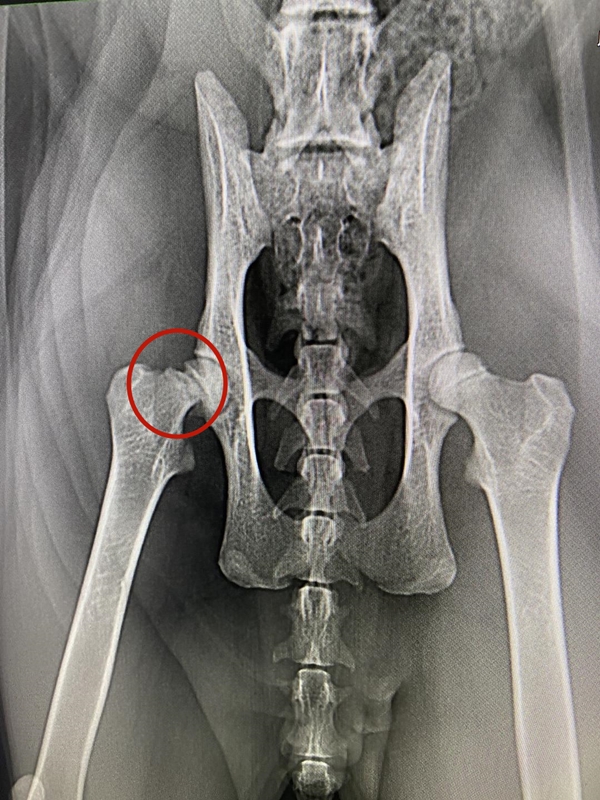

某位铲屎官在卧室玩游戏时,让猫咪独自在客厅玩耍。突然听见猫咪叫了一声,之后就再没动静了。铲屎官去客厅一看,找到了趴在角落里的猫咪,状态看起来不太好,把它放在地上观察,猫咪好像腿骨折了。铲屎官立即把猫咪送到医院去拍片,医生说右腿的腿根处有裂开,需要做手术。推测猫咪可能是从高处摔下时导致受伤。

可铲屎官无论如何也想不通猫咪是怎样受伤的,客厅里最高的地方就是一台小冰箱,但也不足一米六而已。怎么就会骨折了呢?

而另一位铲屎官,他的猫咪在七楼阳台上玩耍时不慎踩脱脚摔了下去。在草坪上找到猫咪时,它一动不动,嘴角还淌着血,低哼了两声再无动弹。送到医院抢救时,医生检查后发现猫咪不仅右后脚骨折,心脏、肝脏和膀胱还严重出血,最终因抢救无效死亡。